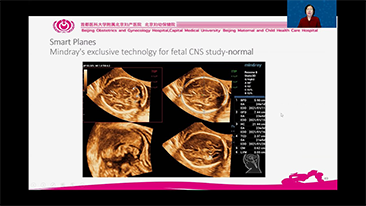

WomenŌĆÖs health is the foundation of health for all and is especially important for countries with aging populations and low fertility levels. MindrayŌĆÖs solution protects multiple life stages, including reproduction, prenatal and intrapartum, and postpartum pelvic floor, with accurate images and efficient and easy-to-use intelligent applications to help caring womenŌĆÖs health in all aspects and cycles.